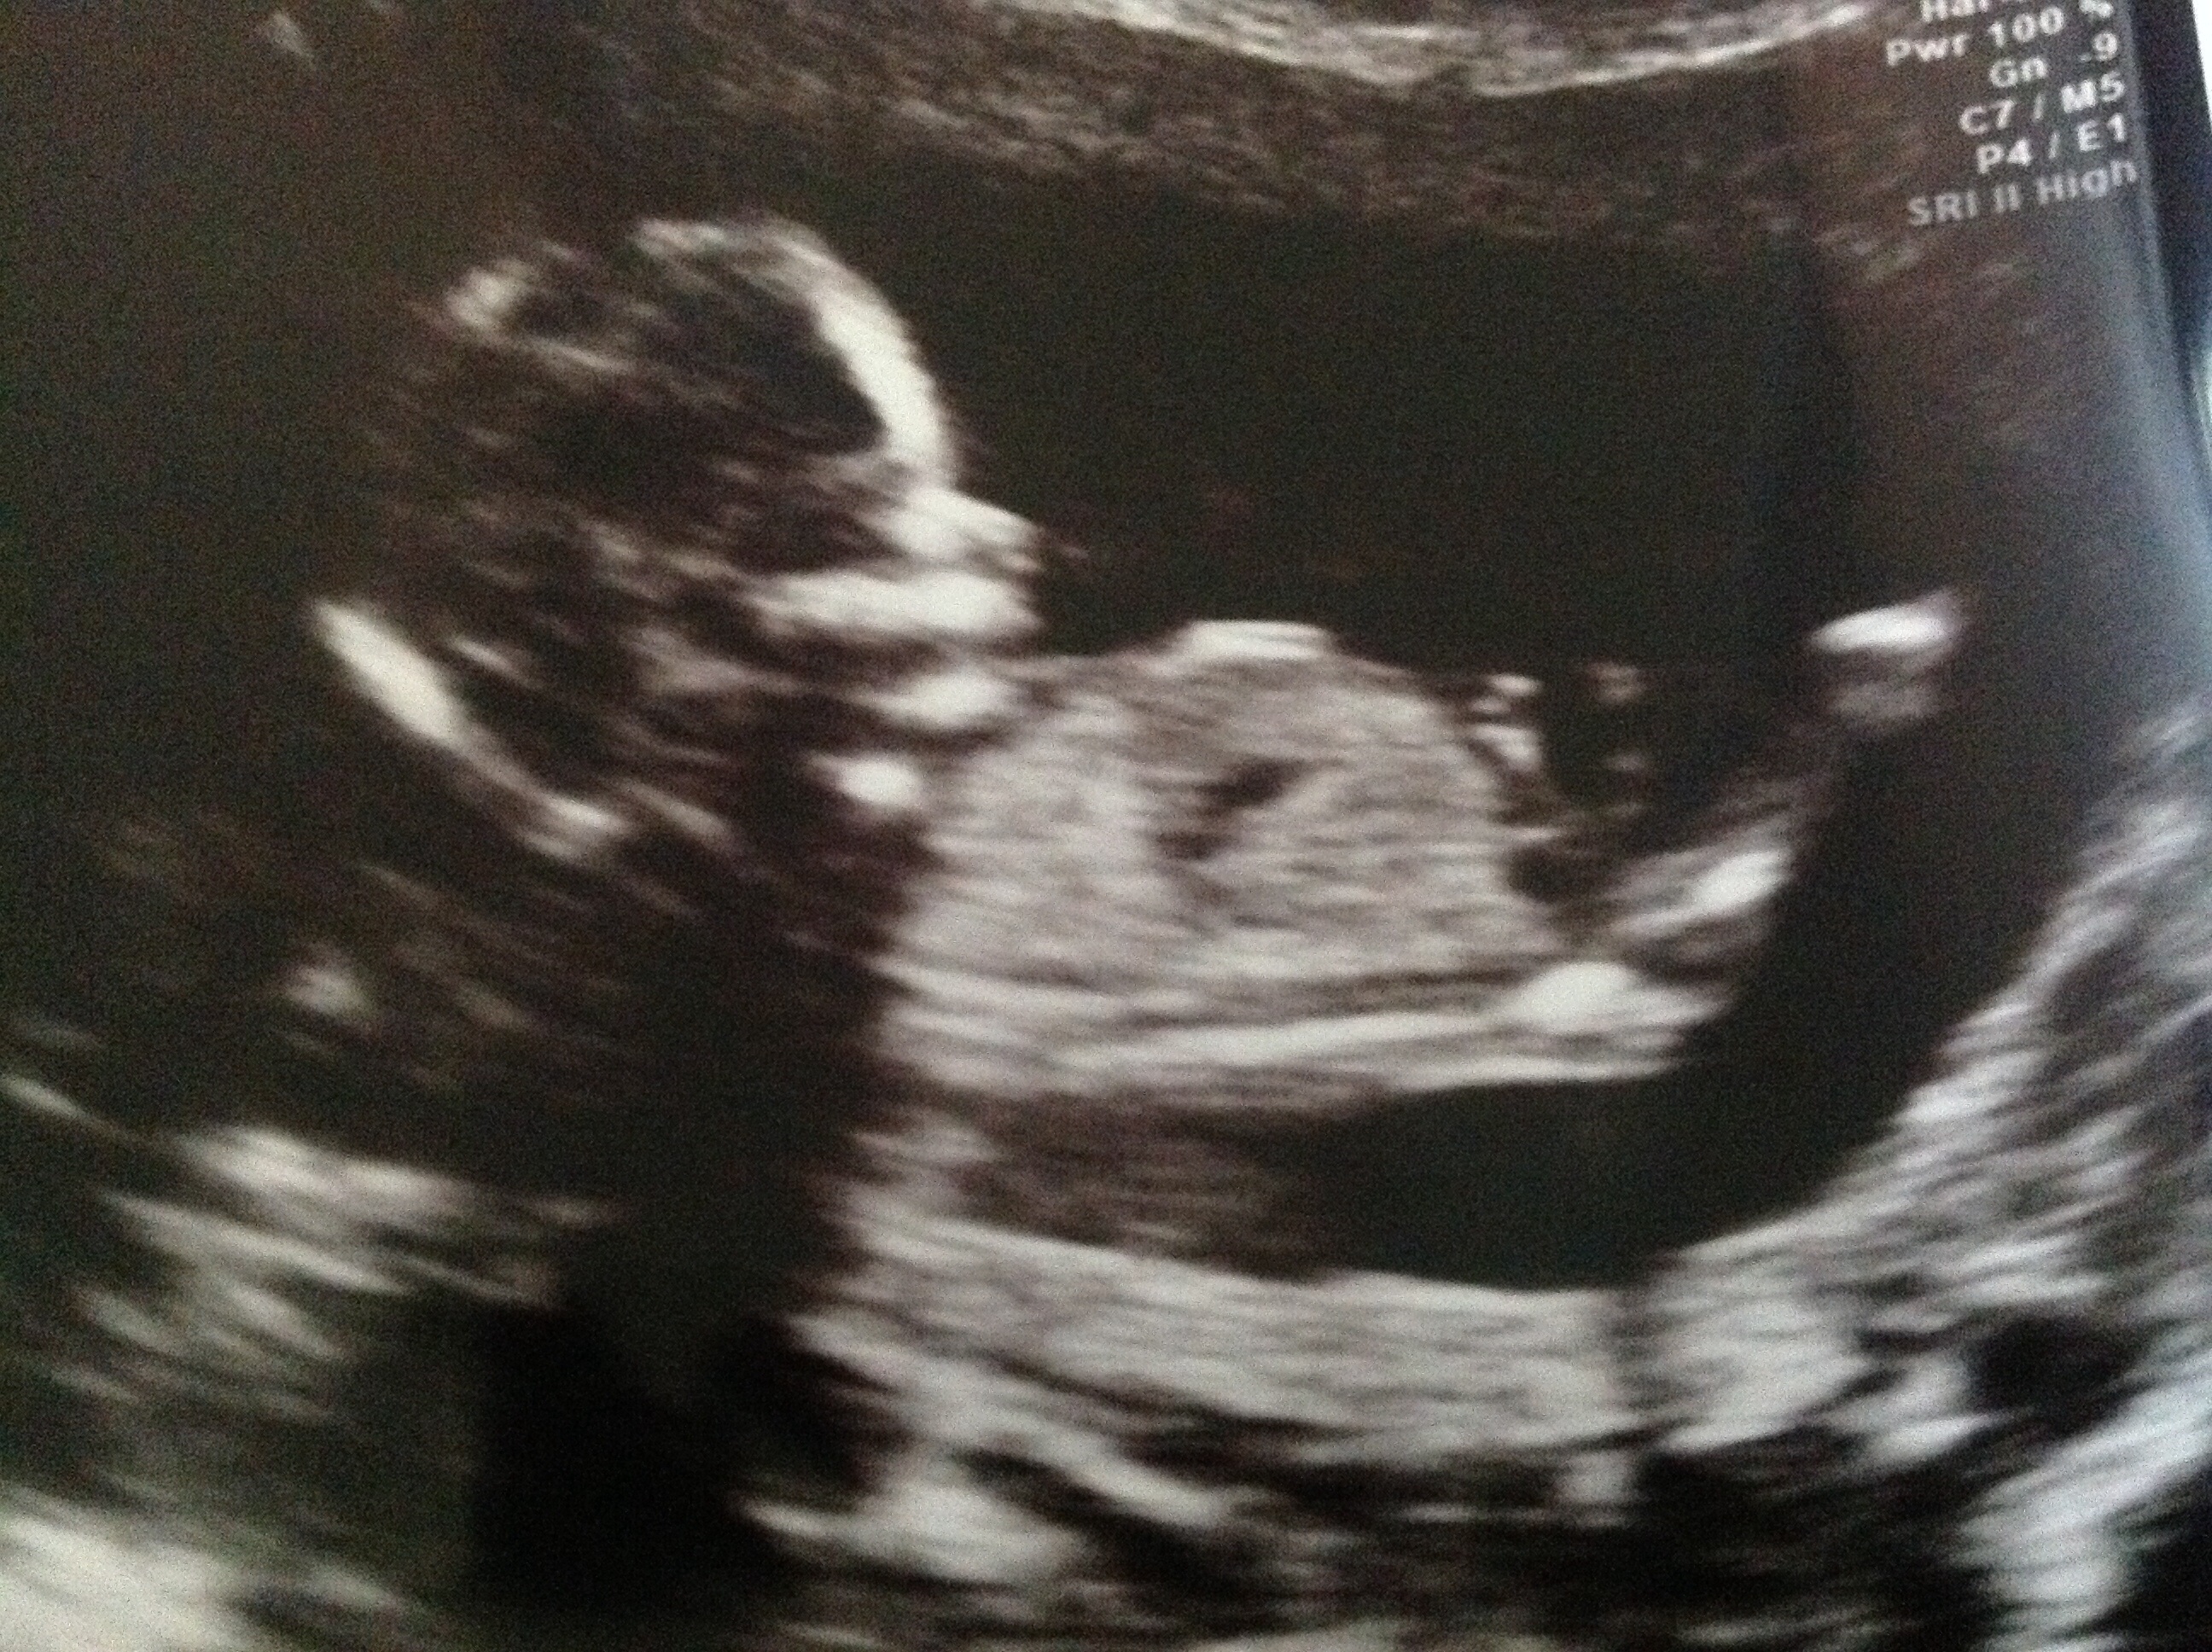

Hi ladies not sure if the nub is visible but just wondered what others think the picture was taken at 13 weeks 5 days thanks xAttachment 19211

Hmm... maybe a boy. Congrats!

Thinking blue

blue

I'm also thinking boy

boy also

I don't know that that's the nub. Beautiful baby, though!